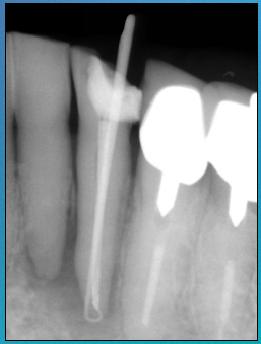

Uiteraard dient een X-foto te worden gemaakt. Soms is er een periapicale lucentie te zien.

Differentiaal diagnostisch moet er rekening worden gehouden met een fractuur. Gebruik van de behandelmicroscoop vergemakkelijkt de diagnose.